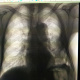

Мужчина поступил по"  скорой".

Жалобы; задыхается.

Признаки полисегментарной пневмонии в н/доле слева на фоне старых фиброзных изменений. Осумаованный паракостальный гидроторакс.Клинико-лабораторное сопоставление. Динамика.

Инфаркт-пневмонию исключайте. КТА.

Левосторонняя пневмония в S5, S8. Рентген контроль через 7-10 дней.

+ 1 , изменения и в нижней доле и в верхней

Вот прямая проекция ( та же дата) баче качеством. Новообразований не имелось.

Для правильной интерпретации рентгенограмм нужны данные анамнеза, клиническая информация и архив. Возможно, просто шварты.